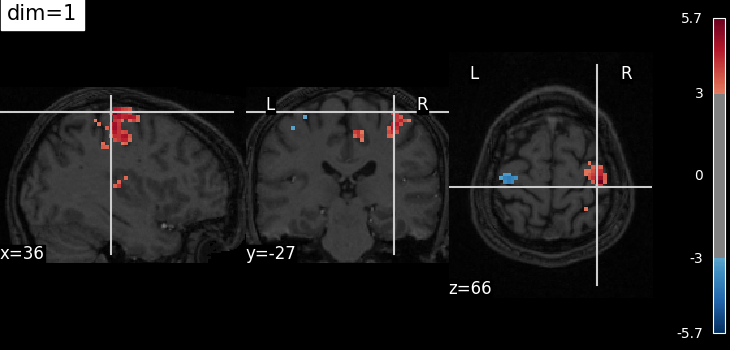

The dim argument controls the contrast of the background.

dim modifies the contrast of this image: dim=0 leaves the image unchanged, negative values of dim enhance it, and positive values decrease it (dim the background).

Plotting with more decrease in contrast with dim=1¶

plot_stat_map(

localizer_tmap_filename,

bg_img=localizer_anat_filename,

cut_coords=cut_coords,

threshold=3,

title="dim=1",

dim=1,

)

show()